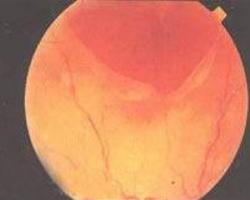

1900年Terson首先报道了颅内出血可以是玻璃体出血的原因,并且认为这种眼-脑综合征是蛛网膜下腔出血的征象,称为Terson综合征。